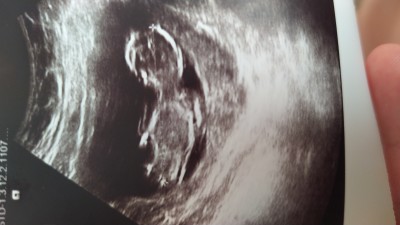

Kizlar anlayan varsa bakabilir mi Dr söylemedi bende mrk ediyom şimdiden teşekkürler

Gebelik haftası 13+2

Kiz bebek gibi hissettim Rabbım hayirli saglikli bi şekilde kucağımıza almayı nasip etsin bebislerimizi